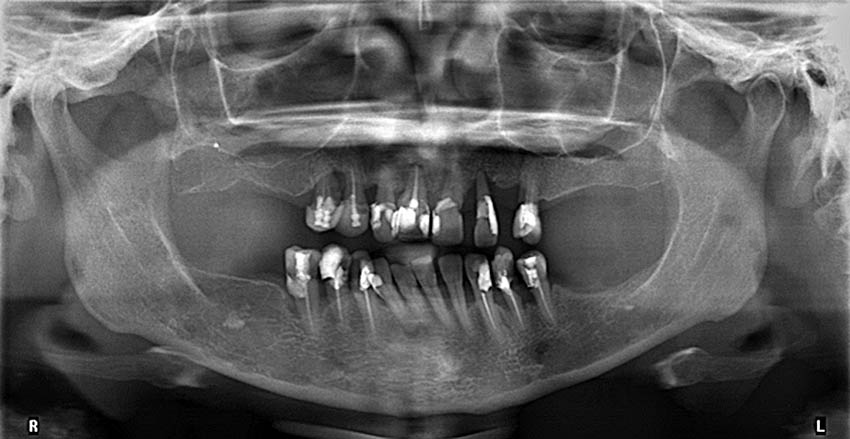

Αναφορά περιστατικού

Μία ασθενής ηλικίας 47 ετών διαγνώστηκε με προχωρημένη γενικευμένη περιοδοντική νόσο, με πολλά ελλείποντα δόντια, απουσία προσθετικών αποκαταστάσεων στην οπίσθια περιοχή του στόματος, περιακρορριζικές βλάβες και μία ατελή ενδοδοντική θεραπεία. Η ασθενής χρειαζόταν μία εκτεταμένη και διεξοδική οδοντιατρική θεραπεία.

Για να δημιουργηθεί ένα προκαταρκτικό σχέδιο θεραπείας, είναι απαραίτητο να εφαρμοστεί μία αρχική θεραπεία (υγιεινή του στόματος), ώστε να ελεγχθεί η ύπαρξη κινήτρου από πλευράς της ασθενούς να συνεχίσει την πολύ εξειδικευμένη θεραπεία όπως επίσης και για να εκτιμηθεί η πρόγνωση των εναπομεινάντων δοντιών της.

Η λεπτομερής κλινική εξέταση θα περιελάμβανε, μεταξύ των άλλων, στοιχεία σχετικά με το βάθος των περιοδοντικών θυλάκων (ΒΘ), την αιμορραγία κατά την ανίχνευση (ΑΚΑ) και τον δείκτη πλάκας (ΔΠ).

Στην περίπτωση που υπάρχει μία σημαντικά βαρεία νόσος, μεγάλη κινητικότητα των δοντιών και πολλά ελλείποντα δόντια, συνιστάται να διεξάγονται μοριακές-βιολογικές εξετάσεις για να πραγματοποιείται μία ποσοτική αξιολόγηση των περιοπαθογόνων.

Πριν τη θεραπεία, η ασθενής υποβλήθηκε σε διαδικασία υποουλικού καθαρισμού με ξέστρα υπερήχων. Μετά τον καθαρισμό, η κλινική κατάσταση της ασθενούς βελτιώθηκε. Στη συνέχεια, εφαρμόστηκε ένα laser Nd:YAG για την αποστείρωση και την απολύμανση των περιοδοντικών θυλάκων (Εικ. 3 έως 7) και laser Er:YAG για την απομάκρυνση της υποουλικής τρυγίας (Εικ. 8 έως 12).